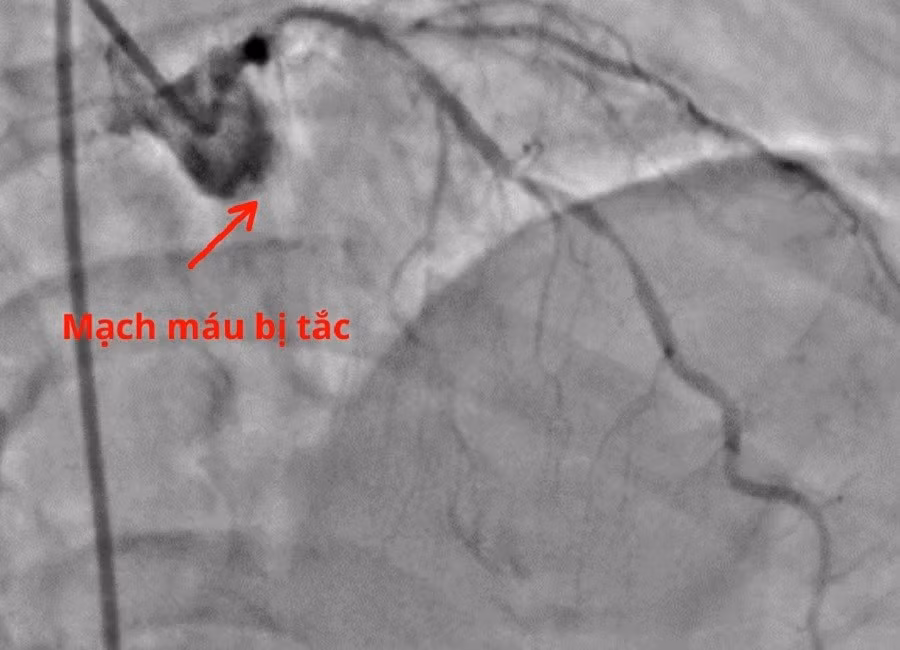

Nhánh mũ động mạch vành bị tắc hoàn toàn là nguyên nhân khiến người bệnh rơi vào nguy kịch

Khi huyết áp được duy trì bằng thuốc vận mạch, ông T. được chuyển thẳng vào phòng Thông tim. Trong quá trình can thiệp, ê kíp bác sĩ phát hiện nhánh động mạch vành mũ của người bệnh bị tắc hoàn toàn. Các bác sĩ tiến hành tái thông mạch vành bằng bóng giúp khôi phục dòng máu nuôi tim mà không cần đặt stent, từ đó giảm nguy cơ tái hẹp về sau.